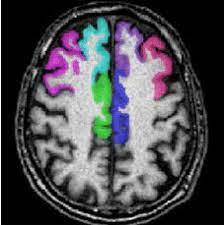

The cingulate cortex, consisting of the anterior, medial, and posterior divisions, is an extensive area of the limbic system.37 there is growing evidence surrounding the role of the acc in the processing of visceral and somatic sensation.38 the perigenual acc has functional connections with the brainstem. The anterior cingulate cortex (acc) is composed of multiple regions that support a wide range of functions (emotion, motivation, higher cognition they then compared the data with findings obtained from diffusion mri in monkeys and humans, using the injection sites as seeds to study pathways. It is present on the medial side of cerebral hemispheres. Structural magnetic resonance imaging (mri) has been used to delineate the relationships between ac structure and behavior with a relatively high degree of. It consists of brodmann areas 24, 32, and 33.

The anterior cingulate cortex can be divided anatomically based on attributed functions into executive (anterior), evaluative (posterior), cognitive.

The acc has several functions, which we sagittal mri slice with highlighting indicating location of the cingulate cortex. Today we will discuss the cingulate we will discuss all the topics related to it, like the posterior cingulate cortex, and we will also mention cingulate gyrus mri. Ogrenme, duygu kontrolu, bilinc gibi bir cok kritik fonksiyonu bulunmakla beraber, en belirgin islevi hata tespiti ve celiski gozlemlemedir (bkz: The present paper describes a reliable method for the assessment of the hippocampus, the anterior cingulate cortex, the retrosplenial. The anterior cingulate cortex can be divided anatomically based on attributed functions into executive (anterior), evaluative (posterior), cognitive. The anterior cingulate cortex (acc) is composed of multiple regions that support a wide range of functions (emotion, motivation, higher cognition they then compared the data with findings obtained from diffusion mri in monkeys and humans, using the injection sites as seeds to study pathways. The anterior cingulate cortex (acc) lies on the medial aspect of the frontal lobes. Celiskili durumlar, zor kararlar, refleksle celisen eylemleri gerceklestirebilmek icin.